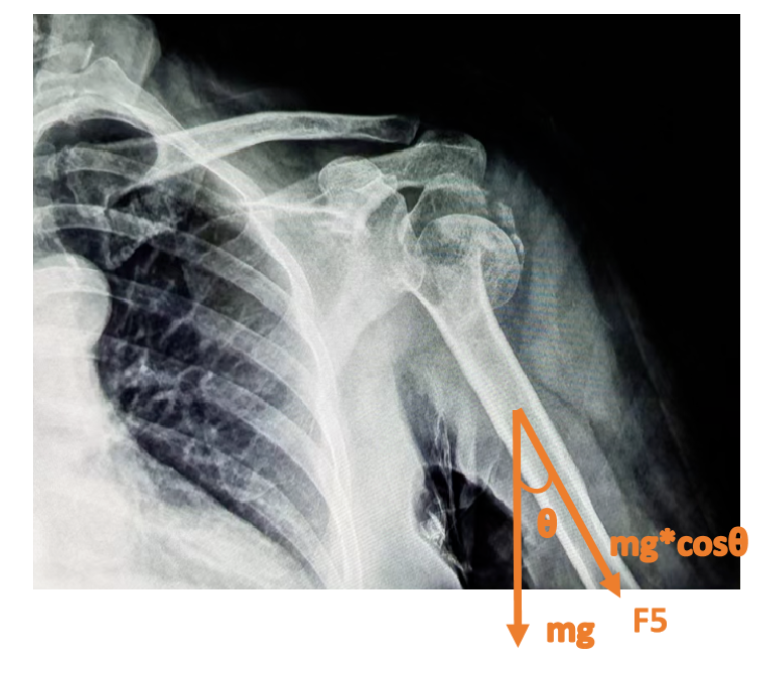

第四部分的力F5。肘与前臂夹角110°左右悬挂,使得肱骨干重力在肱骨干上的分力(mg余弦∠身体与上臂之夹角)较大,同时使在断端嵌插处得到牵拉修复的空隙。

诸力使得近断端沿肱骨干向上,远断端沿着肱骨干向下,骨折修复因子在这样的力学系中进行着正相“光合作用”——即成骨细胞、破骨细胞沿力学方向进行最大化的修复与重建。